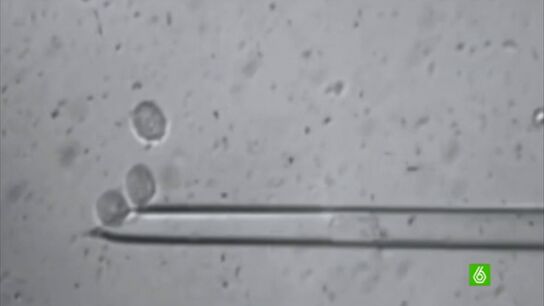

Se extrae el ADN del óvulo de una donante. Se inserta una célula de piel, de otro donante con su ADN y cuando se fusionan, es como si el ovulo hubiera sido fecundado. La diferencia con lo habitual es que este solo tiene un ADN. A los cinco días se para el desarrollo del embrión y ahí están las células madres que luego se cultivan. De ahí saldan células de cualquier tipo.